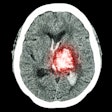

3D printing enhances CT segmentation for brain disease